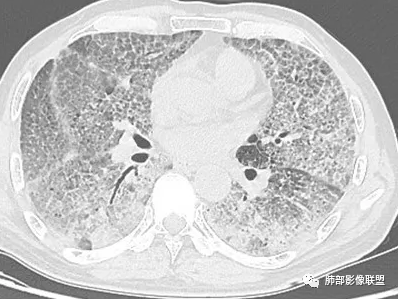

中期:孢子菌在肺泡腔内大量繁殖,引起炎性渗出及肺泡上皮增生,肺泡液内含有滋养体的嗜酸性渗出物及纤维蛋白和脱落的上皮细胞,Ⅱ型肺泡上皮细胞增殖修复受损的肺泡毛细血管间膜,肺间质内巨噬细胞、浆细胞和淋巴细胞增殖导致间质性肺炎,就是说有肺泡腔的密度增高,也有间质的增厚,整个肺受累区域密度都增高,形成以肺门为中心双侧对称的弥漫性磨玻璃样改变,胸膜下较少累及,呈典型的月弓征,采用积极的对症治疗后,大多数病变可吸收消失。

注意肺孢子菌肺炎的肺部影像看上去比较“干”,不会呈现重力趋势。肺血管影及支气管影都比较清楚,尤其是含气支气管影,常常会衬托得格外清晰。

晚期:修复最终导致间质纤维化改变,双肺小叶间隔明显增厚,肺叶呈纤维状、条索状、网格状改变,支气管牵拉性扩张和蜂窝肺,HRCT病灶显示为碎石路征样改变,是本病的特征表现之一,该征象出现表示肺泡、肺间质同时受累,是病变进展的重要表现。肺气囊是肺孢子菌肺炎较常见的影像学特征,多见于晚期,多分布于肺上叶或肺周边, 也可发展到整个肺实质,其形成是由于肺实质的破坏。肺气肿可破裂引发自发性肺气胸、纵隔及皮下气肿。